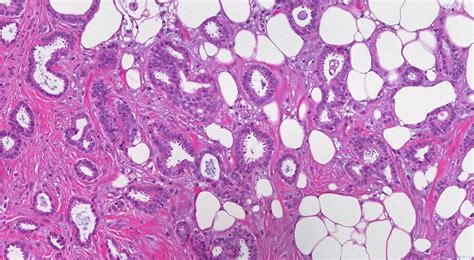

So, what exactly is invasive ductal carcinoma, or IDC? Let’s get down to brass tacks. Invasive ductal carcinoma of the right breast is the most common type of breast cancer. It originates in the milk ducts, which are the tiny tubes that carry milk to the nipple. When the cancer cells break through the wall of the duct and invade the surrounding breast tissue, it’s then classified as invasive . Think of it like a tiny seed sprouting and growing beyond its designated pot. This invasion means the cancer has the potential to spread, or metastasize, to other parts of the body, such as the lymph nodes or even more distant organs. It’s a serious diagnosis, no doubt, but understanding its nature is the first step in combating it. The key word here is invasive , as opposed to in situ , where the cancer cells are contained within the duct and haven’t spread. The ductal part tells us where it started, and the carcinoma simply means it’s a type of cancer that begins in epithelial cells, which line surfaces like the inside of ducts. When we talk about the right breast , it’s a specific localization that helps medical professionals pinpoint the exact location of the malignancy for treatment planning and record-keeping. This specificity is vital. In the realm of medical coding, precision is king, and that’s where the ICD-10 system comes in. It’s a standardized way for healthcare providers to classify and code all diagnoses, symptoms, and procedures. Each code tells a story, and for invasive ductal carcinoma of the right breast, that story is one of a specific, prevalent form of cancer requiring targeted medical attention. We’ll explore the specific ICD-10 codes associated with this diagnosis later, but for now, it’s good to have a solid grasp of what we’re dealing with when we hear this term. The implications of this diagnosis extend far beyond the patient, impacting healthcare systems, research efforts, and public health initiatives. Therefore, accurate coding is not just an administrative task; it’s a fundamental component of effective healthcare delivery.